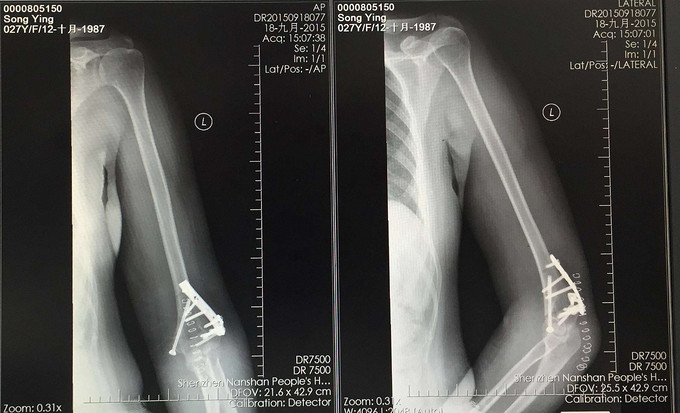

查体:患肢肿胀畸形,肘关节活动受限,感觉血运未见异常。 X线:右肱骨远端骨折 CT:右肱骨远端骨折,骨折线波及关节面

右肱骨远端骨折 行右肱骨远端骨折切开复位内固定术